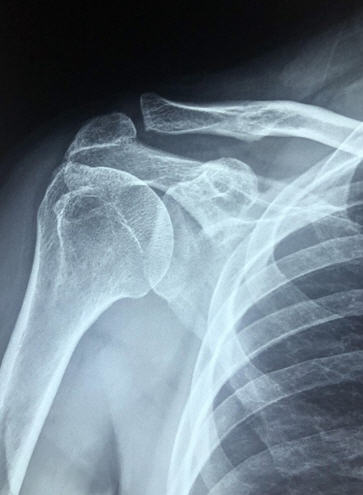

✔ 3. 회전근개 손상 또는 파열

팔을 움직일 때 안정성을 제공하는 어깨 힘줄인 회전근개가 찢어지거나 약해지면 발생하는 상태입니다.

✔ 4. 석회화 건염

회전근개 힘줄에 칼슘(석회)이 축적되어 급성 염증을 유발하는 질병입니다.